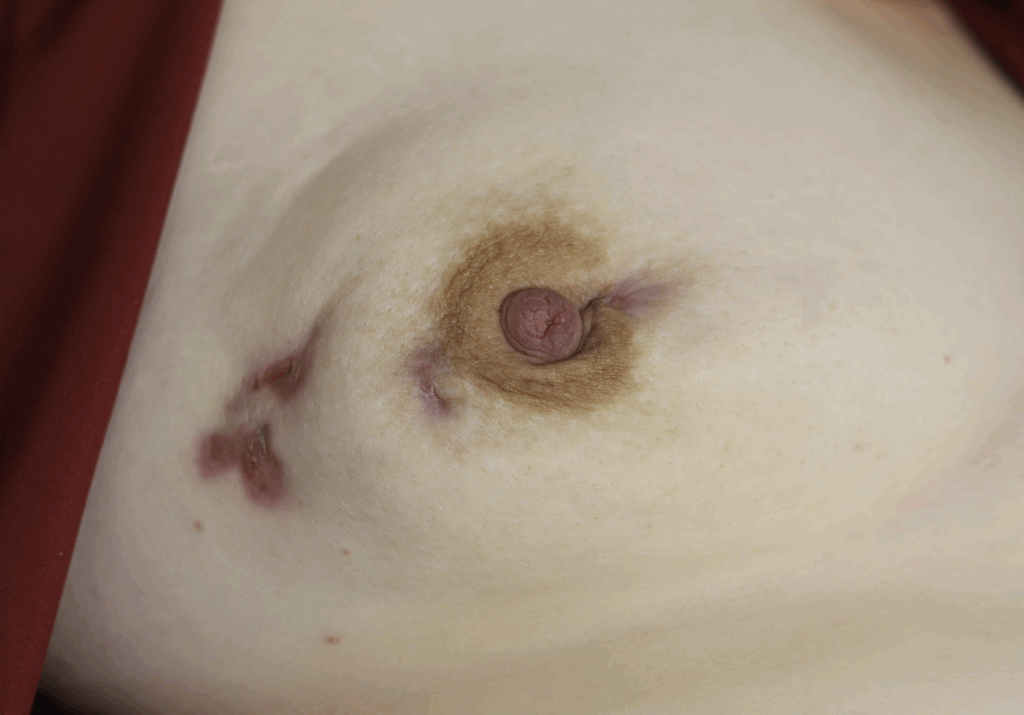

Idiopathic Granulomatous Mastitis (IGM or GM)

Idiopathic granulomatous mastitis (IGM) is an inflammatory disorder affecting the breast of young women in their childbearing years, and can overlap with lactation and pregnancy. It can result in development of painful inflammatory masses, fluid collections, and fistula formation. While breastfeeding from the affected breast in the setting of IGM is safe, many mothers report significant pain and difficulty with latch or milk production.

While some cases of IGM may resolve from a simple mass, many go on to form fluid collections (above and below) that may drain on their own. These are mistakingly called “abscesses.” They are in fact just fluid collections of dead inflammatory cells. Patients need either local treatment with needle drainage of the fluid (NOT large incisions with packing tape, which make inflammation worse) and steroid injection, or oral steroids/anti-inflammatories/immune suppressants.